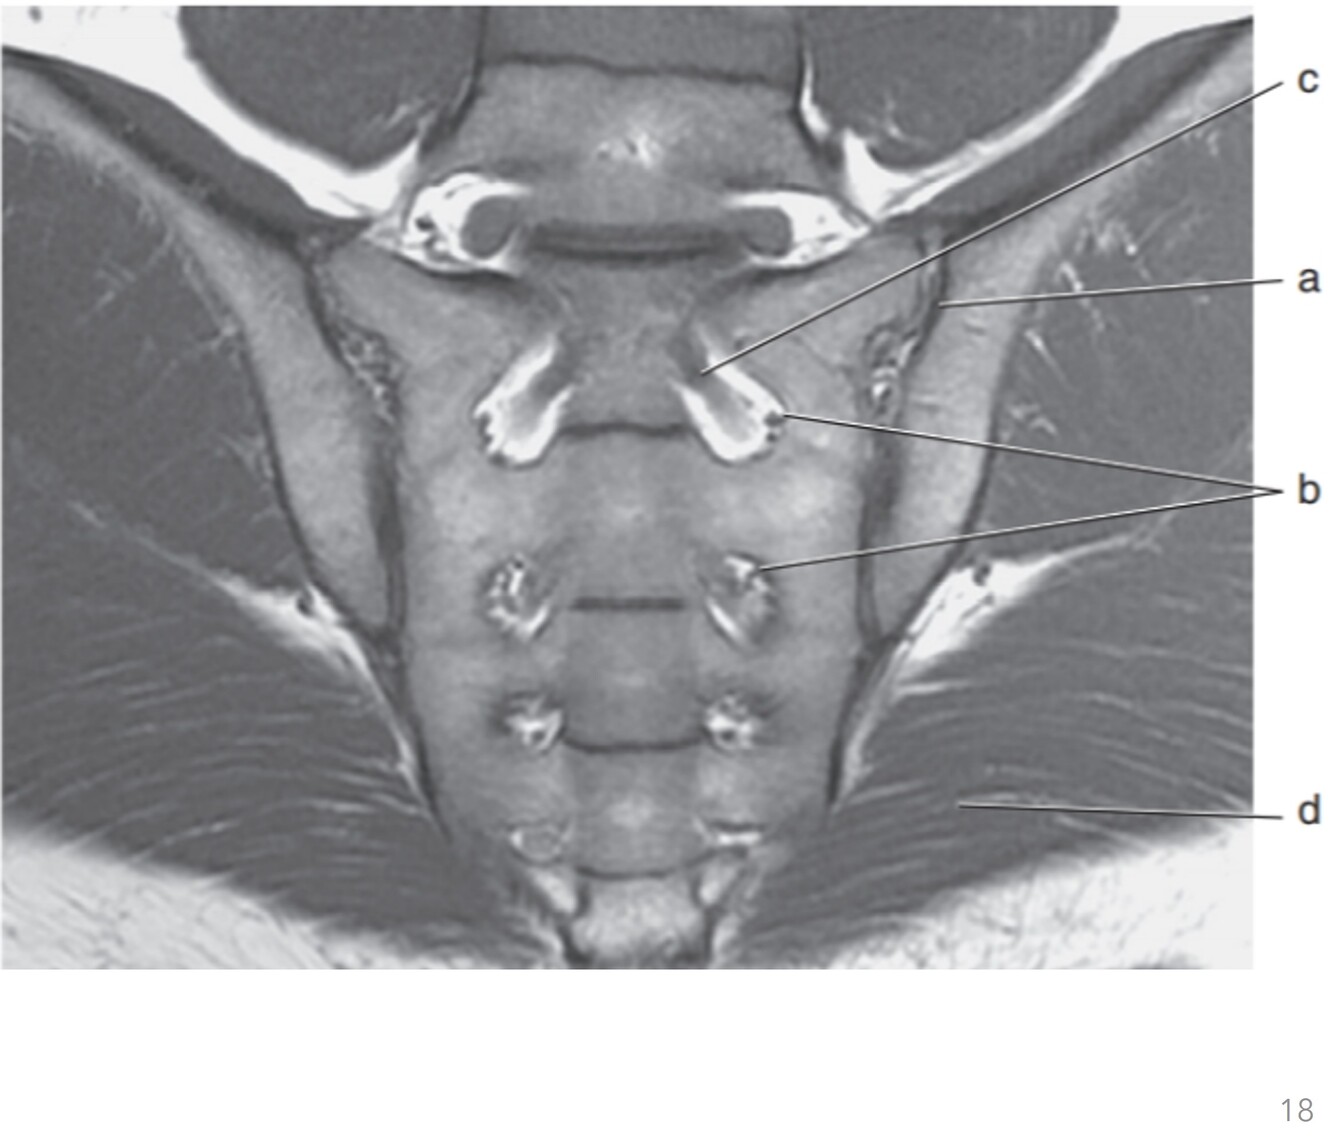

18

Q

Label a,c,d,e,g,h

A

a. Prostate gland

c. Bladder

d. Seminal vesicle

e. Pubic symphysis

g. Rectus abdominis

h. Urethra